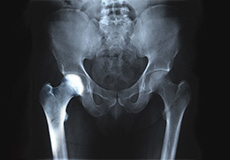

Hip Joint

The hip joint is the largest weight-bearing joint in the human body. It is also referred to as a ball and socket joint and is surrounded by muscles, ligaments, and tendons. The thigh bone or femur and the pelvis join to form the hip joint.

Any injury or disease of the hip will adversely affect the joint's range of motion and ability to bear weight.

The hip joint is made up of the following:

Bones and Joints

The hip joint is the junction where the hip joins the leg to the trunk of the body. It is comprised of two bones: the thigh bone or femur and the pelvis which is made up of three bones called ilium, ischium, and pubis. The ball of the hip joint is made by the femoral head while the socket is formed by the acetabulum. The Acetabulum is a deep, circular socket formed on the outer edge of the pelvis by the union of three bones: ilium, ischium, and pubis. The lower part of the ilium is attached by the pubis while the ischium is considerably behind the pubis. The stability of the hip is provided by the joint capsule or acetabulum and the muscles and ligaments which surround and support the hip joint.

The head of the femur rotates and glides within the acetabulum. A fibrocartilagenous lining called the labrum is attached to the acetabulum and further increases the depth of the socket.

The femur or thigh bone is one of the longest bones in the human body. The upper part of the thigh bone consists of the femoral head, femoral neck, and greater and lesser trochanters. The head of the femur joins the pelvis (acetabulum) to form the hip joint. Next, to the femoral neck, there are two protrusions known as greater and lesser trochanters which serve as sites of muscle attachment.